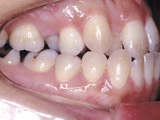

症例2:乱杭歯「歯並びが乱れている」

治療前 治療後